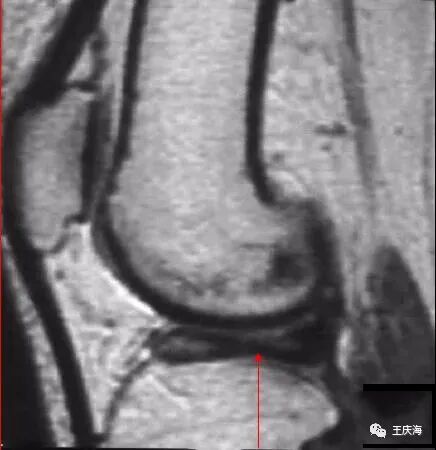

大盘状半月板覆盖75%以上的一侧胫骨平台

矢状面T2WI(上图)显示半月板覆盖整个一侧胫骨平台,形态不规则,信号不均匀。